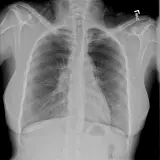

Over 2,100 interactive radiology cases, curated by radiologists for your level of training. Scroll, window, and view cases full screen — just like on PACS. Click linked findings in each writeup to jump straight to them on the image. Cases include sample reports, a focused discussion section, original illustrations, and videos.

Our site includes 3 main courses: Call Preparation, Introduction to Radiology, and Neuro Fellowship.

Call Preparation — our comprehensive curriculum for junior residents preparing for call covering both classic and atypical presentations. Use the call simulator to practice a real call shift — shuffle cases, enter your own preliminary report, and receive constructive AI feedback.

Casos totalmente interativos com as ferramentas que você espera em um PACS — rolagem, ajuste de janela, zoom, movimentação, medidas, ROIs e modo de tela cheia.